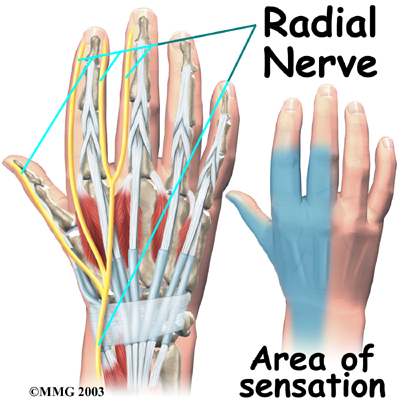

The

runs along the thumb-side edge of the forearm. It wraps around the end of the radius bone toward the back of the hand. It gives sensation to the back of the hand from the thumb to the third finger. It also goes to the back of the thumb and just beyond the main knuckle of the back surface of the ring and middle fingers.